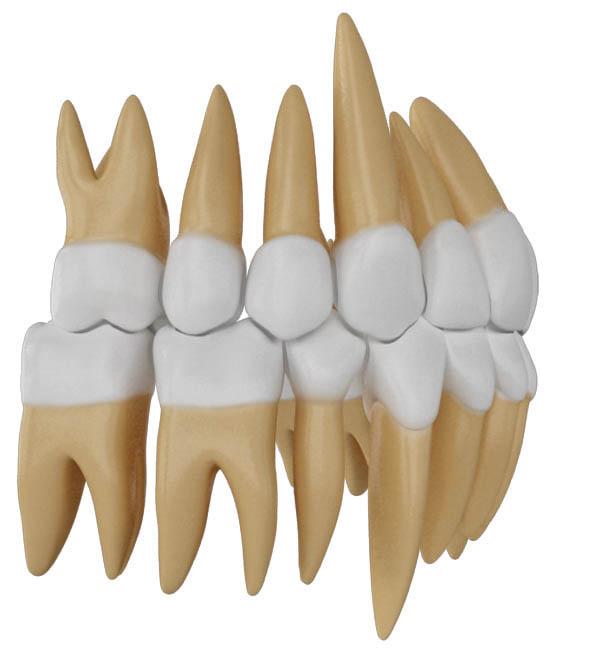

شکل 128-2: پرمولر پایین کشیده شده و فضا بسته شده است و خلف پایین نیم کاسپ حرکت مزیالی نموده ولی اکلوژن هنوز 1.5mm کلاسII است.

شکل 129-2: پرمولر بالا کشیده شد و چون باید اکلوژن کلاسI تمام بشود، حتی اگر خلف بالا اصلاٌ حرکت مزیالی به کمک مینی اسکرو ننماید، باز اکلوژن کلاسI نمیشود.

شکل 130-2: در 5mm کلاسII، وقتی از دو فک میکشیم نتیجه درمان را یک کاسپ کامل کلاسII نمیتوانیم تمام کنیم.